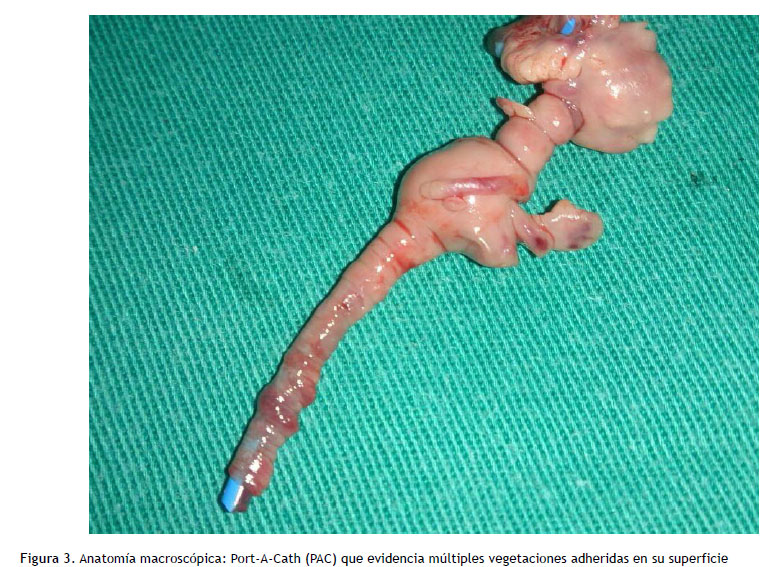

Inició cobertura empírica para endocarditis con imipenem y vancomicina, con resultados de hemocultivos periféricos negativos. No se tomaron muestras de la punta ni del septum subcutáneo. Por la sospecha de endocarditis fúngica, se decide retiro del dispositivo intravascular mediante toracotomía, siendo realizado a las 48 horas del inicio de antibióticos, objetivándose la presencia de importante biofilm (Figura 3), con resultado de cultivo directo de la pieza extraída que reportaba C. parapsilosis (Figura 4). La susceptibilidad de la cepa fue la misma que el episodio previo de candidemia y se dirigió la cobertura antifúngica con caspofungina 70mg EV dosis de carga y luego completó 30 días con 50mg EV/día, posterior al retiro del PAC y negativización de hemocultivos, continuando con fluconazol 800 mg/día por 2 semanas adicionales.